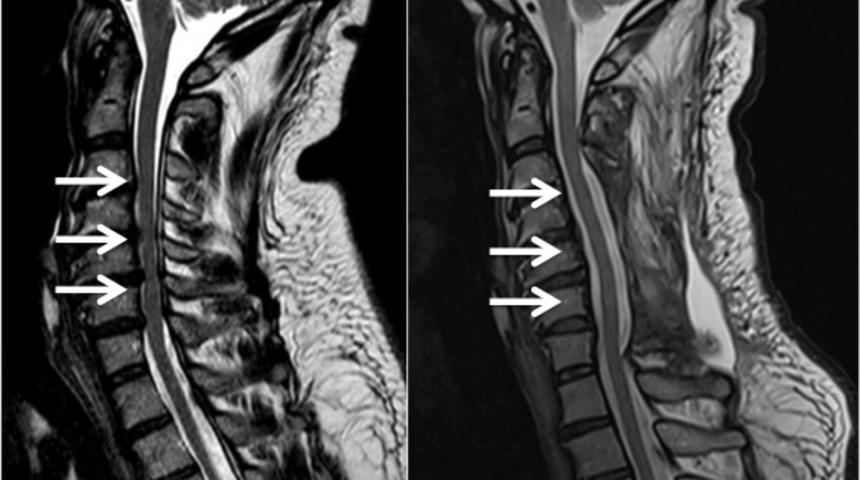

Minimal Invaziv Lomber Dekompresyon anlamına gelen MILD; ABD'de geliştirilmiş ve açık cerrahiye gerek duymaksızın omurga kanalındaki darlıkları gidermeye yarayan güvenilir, yeni bir tedavi yöntemidir. Omurga kanal darlıkları tedavisinde kullanılan MILD ile ilgili merak edilenleri anlatan Girişimsel Nöroradyoloji uzmanı Doç. Dr. Eren Erdem, işlemin hastanede kalmaya gerek duyulmadan yapıldığını söyledi.

Girişimsel nöroradyoloji konusunda uzman bir doktor, görüntüleme (floroskopi) eşliğinde özel ameliyat aletleri kullanarak işlemi gerçekleştirir. Doktor sırttaki küçük bir kesiden girerek, omurga kanalından ufak kemik ve fazla doku parçacıklarını çıkartır. Böylece omurga kanalının sinirlere yaptığı baskı giderilir, hastanın ağrısı diner ve hareket kısıtlaması ortadan kalkar.